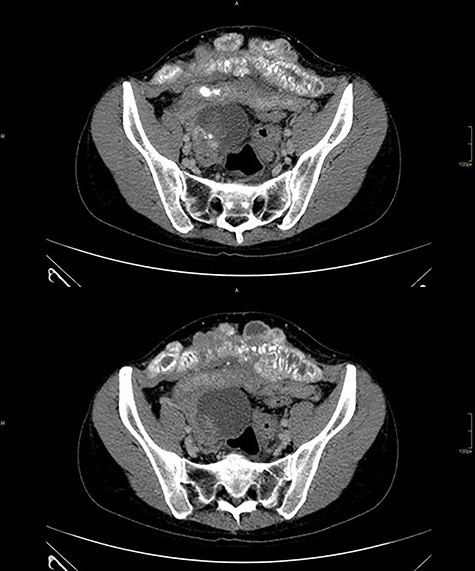

Computed tomography of the abdomen showed solid-cystic lesions in the pelvis (Fig. 2) and a massive expansive lesion in the AW, with soft tissue density and a volume of 334 cm3 (Fig. 3). Between the AW and the pelvic lesions, formation with soft tissue density, heterogeneous enhancement and calcifications are identified, measuring 12.5 × 2.5 cm in the major latero-lateral and anteroposterior axes, compatible with ‘omental cake’.

CT with heterogeneous solid-cystic lesions with contrast enhancement, septations and gross calcifications, in the topography of the uterine attachments, measuring 5.8 × 4.9 × 5.0 cm on the right (74 cm3 volume), 7.8 × 8.7 × 7.9 cm (278 cm3 volume) in the region of the rectouterine pouch and 2.9 × 2.4 × 2.3 cm (8.3 cm3 volume) in the left adnexal region.